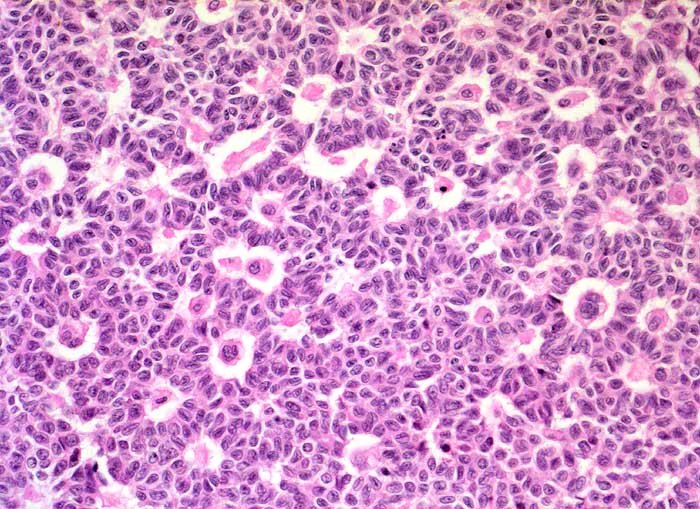

AP/ Granulosazelltumor des Ovars

Granulosazelltumor des Ovars

maligner Tumor

Ovar